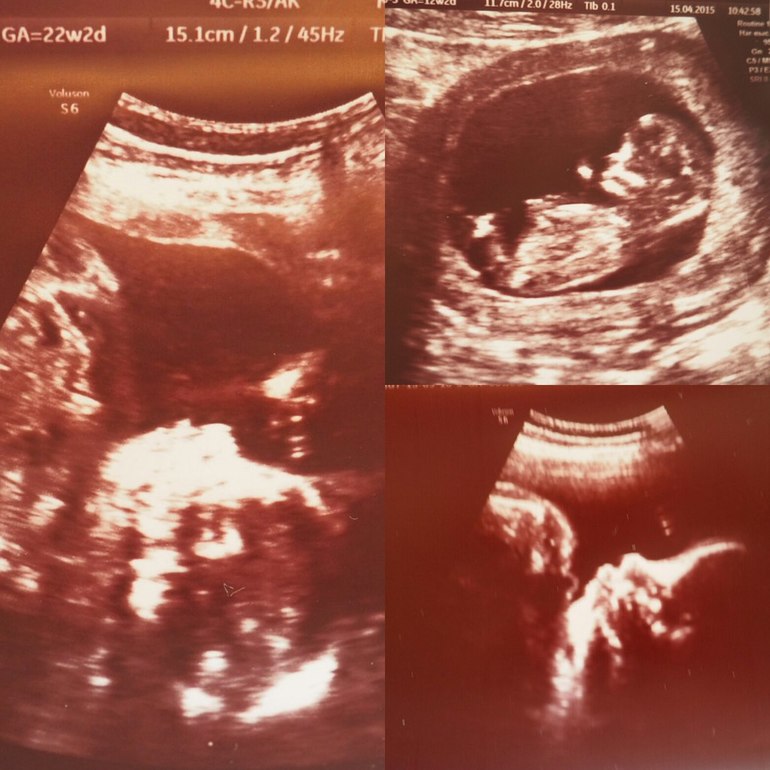

Делала первое УЗИ в 12 недель, очень переживала, но все оказалось хорошо, патологий нет,все в норме.

На 21 недели ходили с мужем на УЗИ,нам сказали,что будет девочка. Так помню этот счастливый день. Каждую неделю животик фотографировала. На УЗИ все с ребенком хорошо, только шейка матки короткая - 21 мм. Положили на сохранение 6 дней, кололи магнезию. Живот иногда тянул, прописали пить Магне В6 и Железо. От Магния живот перестал тянуть, но после того как я его пропила месяц стали появляться коричневатые выделения, но мой Г ушла в отпуск, а медсестра только измеряла живот,вес и давление. Когда стала пить Магний то выделения прекращились. Я судила так - не кровотечение, значит все в норме и боялась сказать на приеме о них. Вот что за дура была? Так виню себя.

На 32 недели пошли делать УЗИ, все в норме, сказали что длинноногая девчонка, плацента в норме, соответствует сроку, околоплодные воды в норме. Это было 10 сентября. А с 5 сентября у меня начались странные выделения. Ну думаю потерплю до УЗИ, если скажут что все в норме и не буду беспокоится. У меня был постельный режим, я мало двигалась, а если и выходила погулять то на промежность уж очень сильно давило, чувствовала дискомфорт, спина ныла и я думала,что ненормальная беременная я, потому как другие на сроке 40 недель гоняют во всю. Нужно мне было обращаться в стационар, ехать в город. А я жила в деревне и ходила к врачам которым не доверяла.